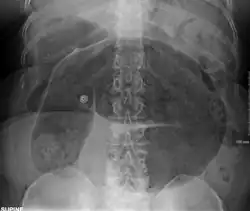

- Abdominal x-ray – tire-like shadow arising from the right iliac fossa and passing to the left

Coffee bean sign in a person with sigmoid volvulus -

Plain X ray of a cecal volvulus -